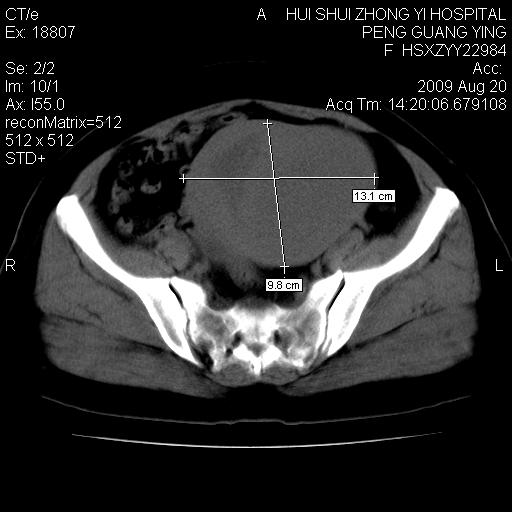

标题: CT21707:女,42岁,因发现下腹部包块2月。 [打印本页]

标题: CT21707:女,42岁,因发现下腹部包块2月。

目前的影像表现显示肿块位于腹腔及盆腔,但具体定位,分清来源较困难,是否来源于卵巢、子宫无法定论,子宫直肠及子宫膀胱周围脂肪间隙尚较清晰,如果患者有过腹腔好或者盆腔手术史,也可以形成不典型的血中,最好手术后定为定性,我期待结果。

软组织密度,与子宫一致。双侧卵巢形态、密度好,不支持来源于卵巢。